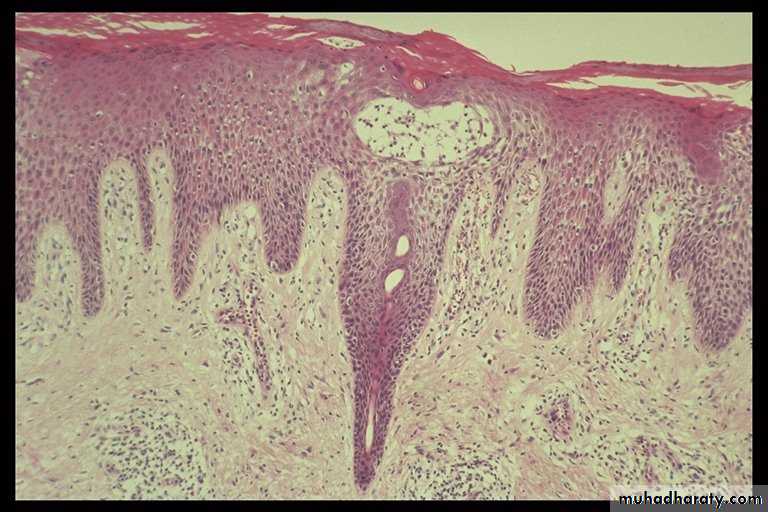

1-Upper dermal oedema, vasodilatation &inflammatory cells infiltration in the dermis.

2-Spongiosis (intercellular oedema of epidermis) which is the hallmark of eczema sometimes with spongiotic vesiculation especially in the acute stage.

3-Focal parakeratosis.

4-In its chronic state: acanthosis & hyperkeratosis.

Dermatopathology: